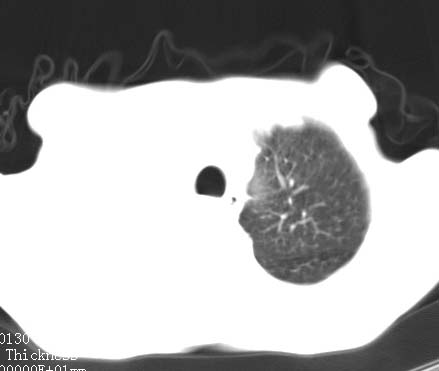

病人女 60岁 咳嗽 气促十余天,大叶性肺炎.

右肺上下叶均见 大片状密度增高影,边界清晰,其内可见支气管充气征,气管支气管通畅。纵膈略向右移位,其内无肿大淋巴结影。首先考虑炎性病变。不排除一些特异性的炎症。不知道发烧吗??wbc高吗??建议治疗后复查!!

看影响还是首先考虑炎性改变,建议实验室检查,还有要警惕炎性肺泡癌,具有的枯枝征象。

看影像还是首先考虑炎性改变,建议实验室检查,还有要警惕炎性肺泡癌,具有的枯枝征象